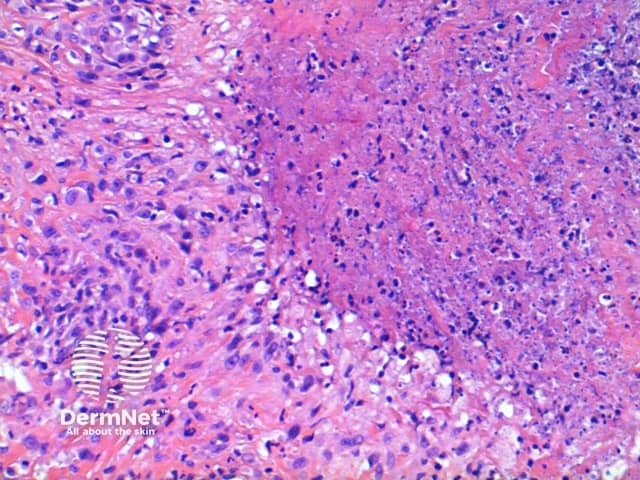

The scanning view of the histology of granuloma annulare shows a granulomatous inflammatory pattern situated within the superficial and mid dermis.

Figure 3